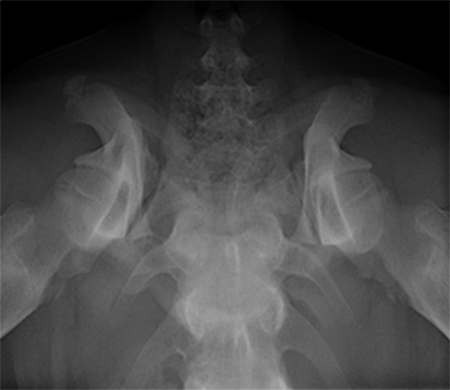

A 5-month-old spayed female labrador retriever puppy weighing 22.0 kg presented with bilateral hind limb weakness and a bunny-hopping gait in the hind limbs. Physical examination revealed bilateral hip instability (positive Ortolani sign) and mild pain on full extension of the hips. Slight crepitus was palpated in the left hip. The gluteal muscles appeared to have mild atrophy. The neurological exam was normal. Radiographic examinations revealed bilateral hip subluxation and a distraction index of 0.5 of the right hip and 0.7 of the left hip (Fig 3). No evidence of osteoarthritis was observed.

A 4-month-old female boxer puppy weighing 15.0 kg presented with bilateral hind limb weakness and reluctance to walk. Physical examination revealed bilateral hip instability (positive Ortolani sign) and severe pain on full extension of the hips. The neurological exam was normal. The radiographs revealed bilateral hip subluxation and a distraction index of 0.65 of the right hip and 0.6 of the left hip (Fig 7). Very mild osteoarthritis was seen and femoral head coverage by the dorsal acetabular rim was good (Fig 8). Angles of subluxation (10° R and 20° L) and reduction (30° R and 40° L) of the hips were measured under anesthesia.